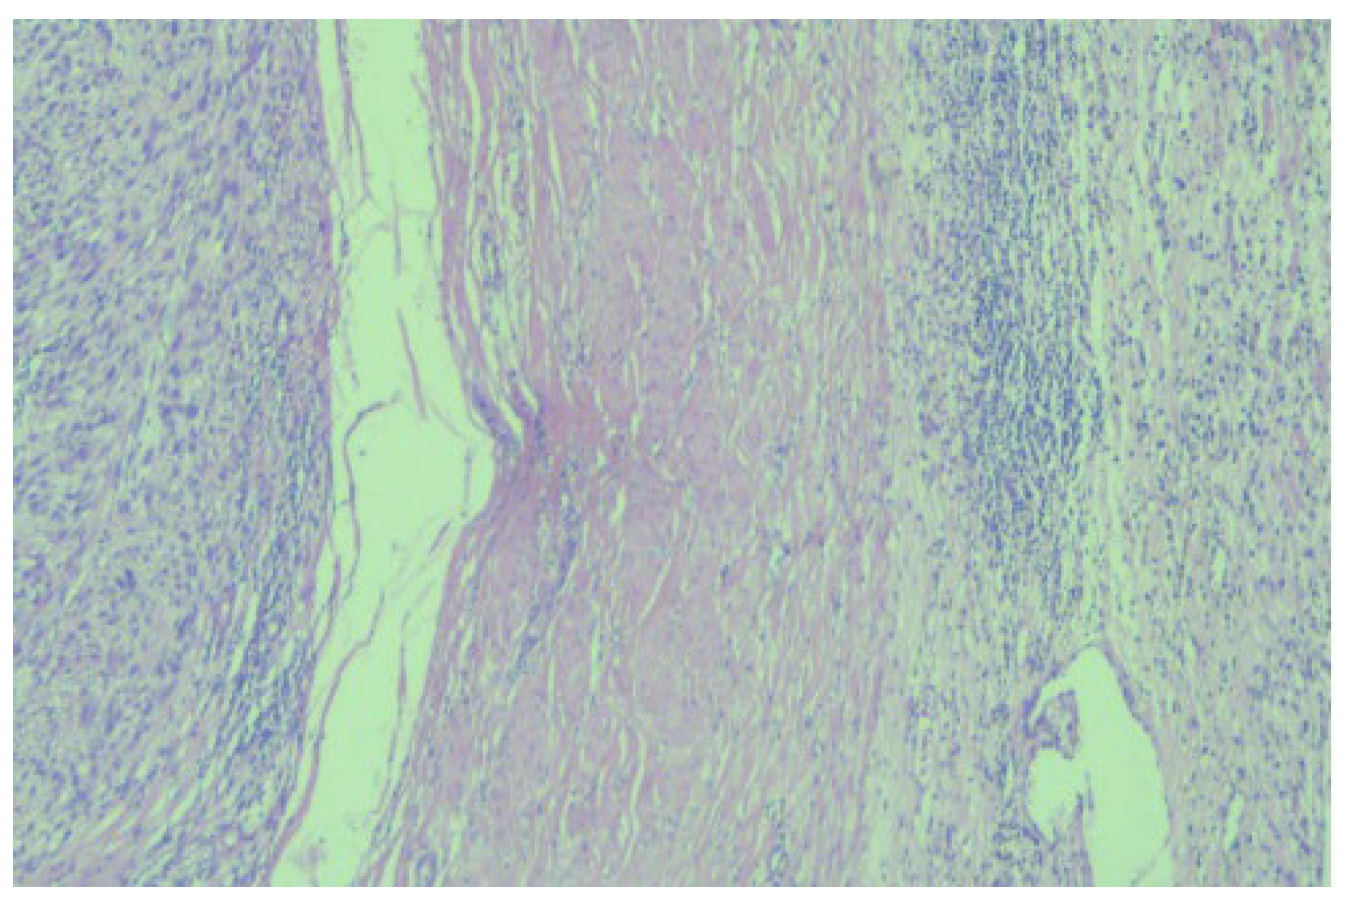

2. Case Report